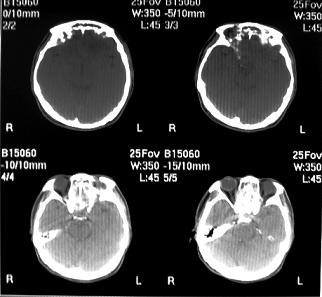

标题: CT10521:男。32岁,副鼻窦ct,请会诊。

男。32岁,鼻塞,流涕一年余。

鼻窦炎伴息肉形成可能,上颌窦内侧壁明显骨质破坏并无挤压,膨胀改变,多不考虑内翻性乳头状瘤.

骨板增生增厚,支持考虑炎症伴息肉,不排除肉翻乳头状瘤

双侧鼻腔内低密度软组织影,骨壁无明显破坏,鼻腔无扩大,双侧上颌窦、筛窦软组织影,窦壁增厚,结合临床考虑鼻息肉合并慢性上颌窦炎。